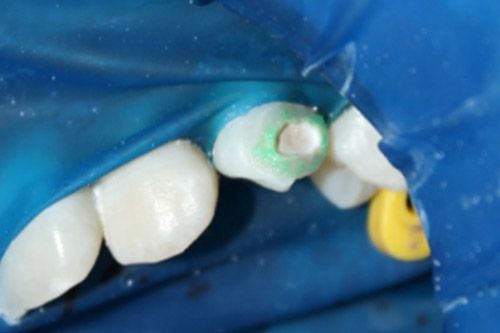

Se observó que una cavidad se había formado, los bordes de esta se grabaron con Icon etch por 2 minutos.

Se aplicó Icon Dry por 30 segundos.

Con la ayuda de un microbrush se aplicó el Icon infiltrant, frotando durante 3 minutos, posteriormente se polimerizó durante 40 segundos.

Se colocó por segunda vez Icon infiltrant en el contorno de la cavidad, pero solo por un minuto y se polimerizó por 40 segundos.